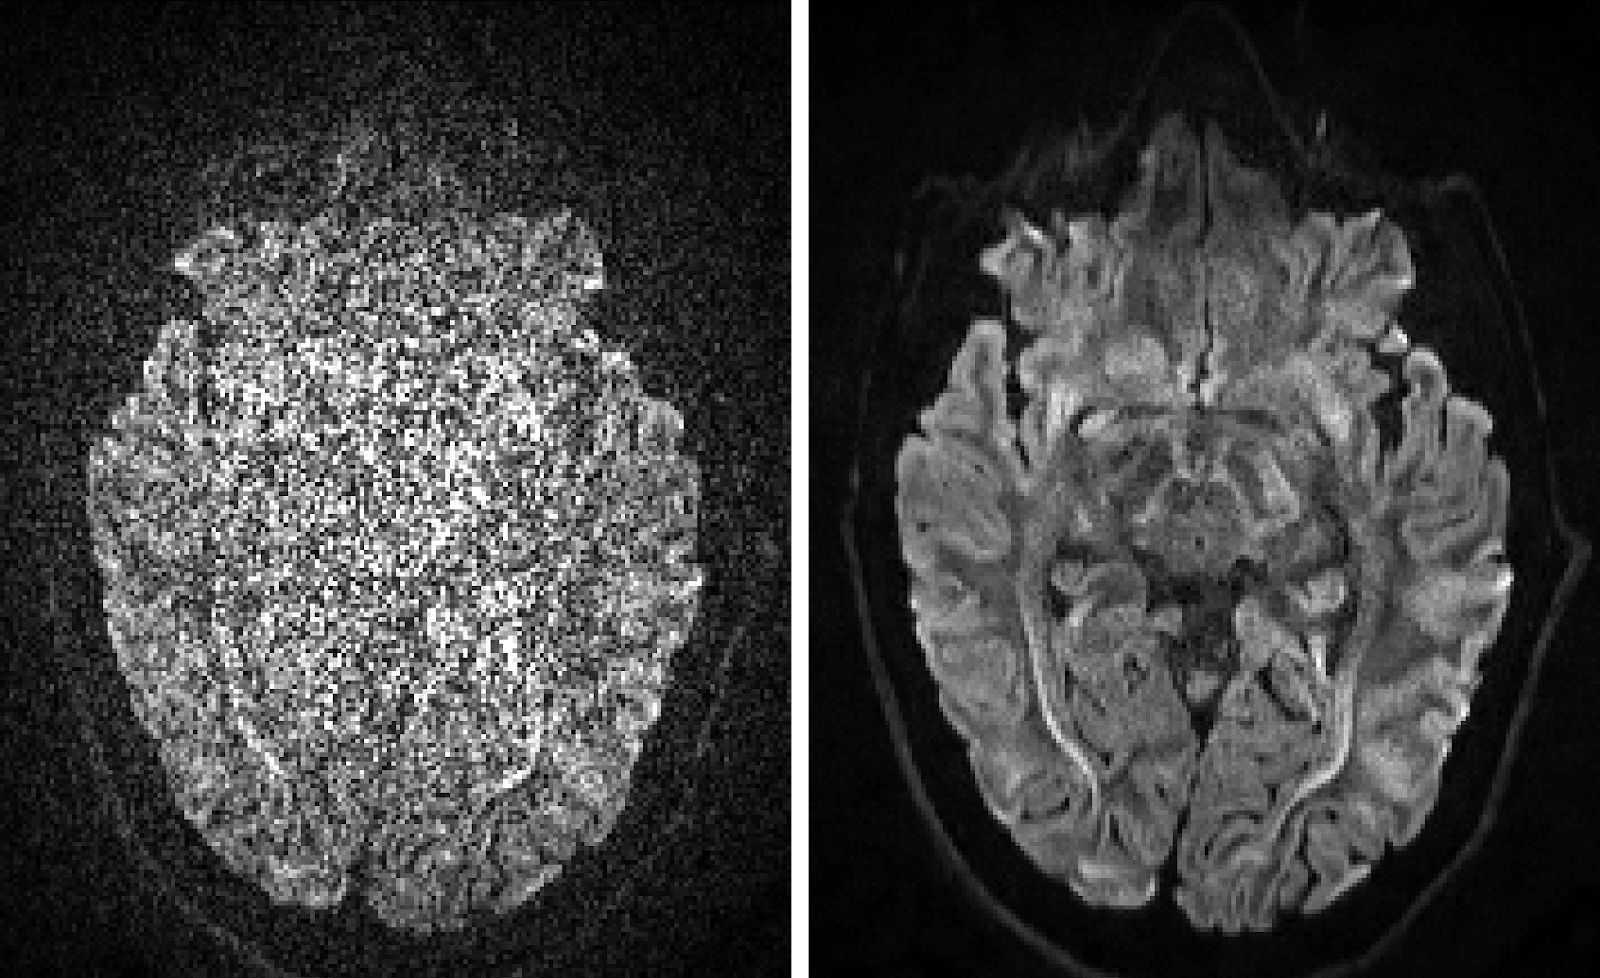

TLDR; MICSI is introducing an innovative image processing algorithm to decrease MRI scan time, increase image resolution, and unlock new diagnostic capabilities using Microstructure Imaging.

Solution: Boosting SNR over the MRI exam using MICSI-RMT.

Our patented approach (pending FDA510k clearance in Q4-2023) uses a self-supervised AI method to learn the noise properties of the MRI exam and remove noise uniformly across all images of the dataset. Our algorithm, MICSI-RMT, can be described as a smart averaging approach, whereby many images of the MRI exam are combined while preserving their unique image properties and discarding the noise. This boost in SNR would be approximately, sqrt(M/P), where M is the number of images included in the dataset, whereas P describes how different the images are (physical properties: proton density, T1, T2, diffusion, etc + artifacts: motion, errors, etc).

With MICSI-RMT, MRI centers will not only be able to provide higher quality imaging but also drastically reduce the scan time (up to 50%). This improved efficiency allows centers to scan more patients per day, enhancing their operational capacity and throughput. Financially, this increase in capacity translates into a significant boost in revenue for every MRI center. By doubling the number of patients scanned daily, we estimate an additional $2 million in annual revenue per MRI scanner. Furthermore, the improved image quality and resolution could lead to more accurate diagnoses, early disease detection, and reducing overall healthcare costs in the long run.